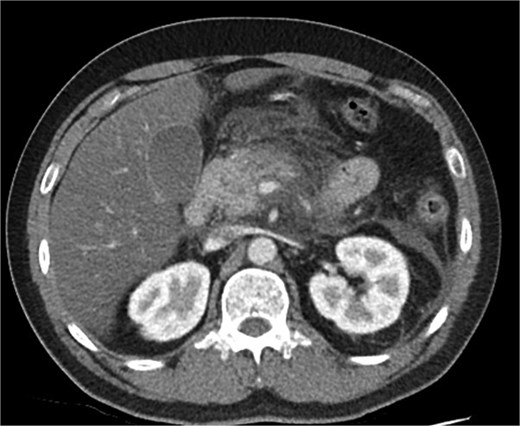

A 39-year-old male presented with one week of worsening epigastric pain radiating to the back, with vomiting, jaundice, and dark urine. His past medical history included depression and alcohol-related liver disease without cirrhosis. On admission he was afebrile, had a soft abdomen with epigastric tenderness worse on palpation, tachycardic, and normotensive. Initial investigations showed a lipase of 2600 U/L, C-reactive protein 238 mg/L, lactate 3.4 mmol/L, and bilirubin 100 μmol/L (Table 1). Abdomen and pelvic computer tomography (CT) demonstrated body and tail pancreatitis, fat stranding, portal vein thrombus, and early necrosis signs, with no choledocholithiasis (Figs 1–3).

Coronal CT image demonstrating body and tail pancreatitis with potential early signs of necrosis.